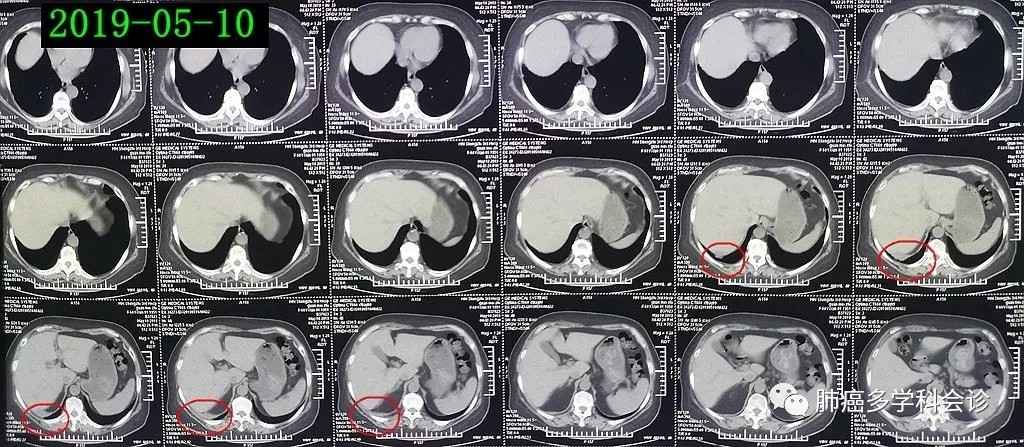

2019-05-10复查CT,与2019-04-05 相比,肿瘤明显缩小:

从此例患者的经过可以看到,沃利替尼对MET基因14外显子突变的非小细胞肺癌有非常好的疗效,用药13天、停药16天后肿瘤即有明显的缩小。但该患者出现了较为罕见的高热和 I 型过敏反应而被迫停止治疗。由于肿瘤组织的PD-L1高表达,患者有可能在靶向药耐药后能从免疫治疗中获益。